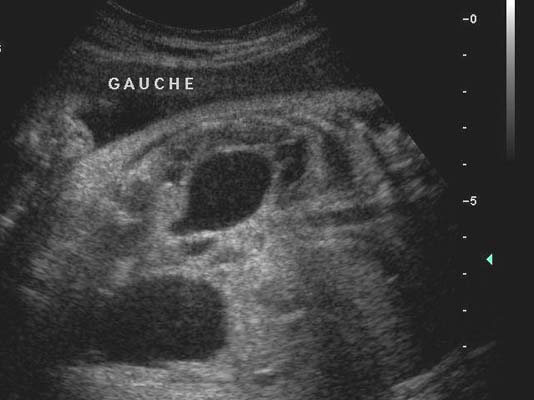

Anéchogène ovalaire